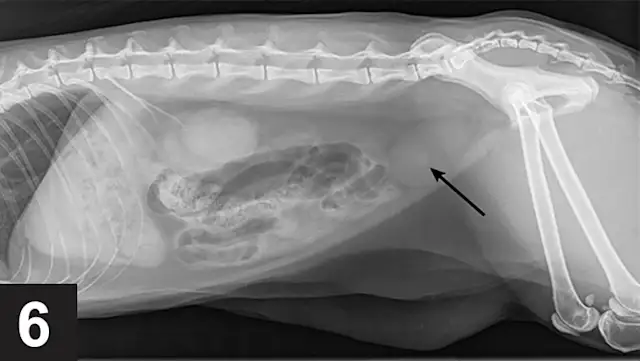

Urate uroliths most commonly form in younger dogs (mean age, 3–4 years) and are usually small, smooth, round or ovoid, and green or brown (Figure 2). They are relatively radiolucent and may require ultrasonography or contrast radiography to be observed (Figures 3–6). Urinary tract infections (UTIs), especially those with urease-producing bacteria, may facilitate ammonium acid urate crystallization. UTI may also occur secondary to urolith-induced mucosal damage and altered local host defense mechanisms. High dietary protein usually increases the urinary excretion of both UA and ammonium ions in affected dogs. Ammonia, produced by renal tubular cells from glutamine, diffuses into the tubular lumen and serves as a buffer for secreted hydrogen ions, thereby forming ammonium ions. Ammonium ions are relatively lipid insoluble and become trapped within the tubular fluid. Acidic urine decreases the solubility of uric acid. AU crystals are usually yellow–brown and spherical with multiple irregular protrusions and are often referred to as thorn apple crystals (Figures 7 & 8).

Monitoring dogs at risk for AU urolith recurrence should include close monitoring for signs of lower urinary tract inflammation or urethral obstruction, as well as periodic evaluation of urine pH and urine sediment for crystalluria. Any UTIs should be treated on the basis of urine culture and sensitivity testing. Recurrence of AU uroliths can be confirmed with imaging which may require ultrasonography or contrast radiography.